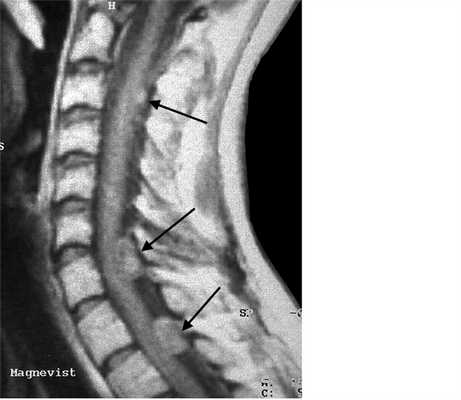

МРТ шейного отдела позвоночника. Нейрофиброматоз тип II. Множественные невриномы (стрелки). Т1-взвешенная МРТ с контрастированием.

Невриномы (шванномы) и нейрофибромы составляют примерно половину опухолей этой локализации и 35% от всех спинальных опухолей. Гистологически невриномы происходят из шванновских клеток оболочек нерва (леммоцитов), прилегающих к заднему корешку. Обычно диагностируются они в возрасте 20 - 50 лет, у мужчин проявляются несколько в более молодом возрасте, чем у женщин. Они почти всегда одиночные, инкапсулированные, располагаются в любом отделе, но чуть чаще в поясничном или верхнем шейном. Множественные невриномы встречаются исключительно редко при нейрофиброматозе типа II. Нейрофибромы состоят из шванновских клеток и фибробластов, некоторые окружают задний корешок. Они почти всегда множественные и связаны с нейрофиброматозом типа I (болезнь Реклингхаузена). От 2 до 12% нейрофибром перерождаются злокачественно, превращаясь в нейрофибросаркомы. Несмотря на различие в гистологии характер роста опухолей одинаковый. Около 15% из них распространяются в экстрадуральное пространство через одно или несколько межпозвоночных отверстий, приобретая вид “песочных часов”. Такой тип роста особенно типичен для шейной локализации. На рентгенограммах рост по типу «песочных часов» может быть выявлен по расширению межпозвоночного ответстия и эрозии корня дуги. Клинические проявления неврином и нейрофибром состоят в радикулопатическом и миелопатическом синдромах.

На МРТ Т1-взвешенного типа и невриномы, и нейрофибромы изо- или слегка гипоинтенсивны по отношению к спинному мозгу. Однако, встречаются случаи и повышенного сигнала за счет сокращения Т1 мукополисахаридами, связанными с водой. Протонная плотность при МРТ повышена, а на Т2-взвешенных МРТ они чаще неоднородные, могут быть очень яркие участки, где имеется высокое содержание воды, и сравнительно низкого сигнала, особенно в центре. Обе опухоли хорошо контрастируются при МРТ. По форме невриномы округлые, границы ровные, четкие. Нейрофибромы вытянуты вдоль корешка, что лучше видно на корональных МРТ. Размеры могут быть самыми различными.

Дифференцировать невриномы и нейрофибромы надо с менингиомами. Последние во всех отделах, кроме шейного расположены чаще кзади, отличаются по форме и обычно изоинтенсивные спинному мозгу на Т2-взвешенных МРТ.